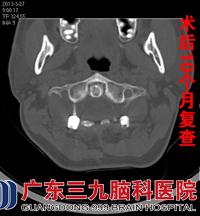

予以颅骨牵引制动,正规药物抗结核治疗,1个月后症状有所缓解,进一步证实了医生的诊断,行颈椎后路减压复位枕颈融合椎根弓钉棒系统内固定手术治疗。术后继续抗结核治疗病情明显好转。2013年3月27日复查颈椎CT示内固定术后改变,环枢关节间隙正常,齿状突低密度影消失,骨质破坏已修复。现随访至术后10个月,颈痛消失,无头胀,无饮水呛咳,四肢感觉肌力正常,活动良好。

CT是早期诊断极有效的方法,CT能清晰地显示骨的破坏和软组织肿胀影,尤其是在早期,能显现较局限的病变,结合病史,考虑为枢椎齿状突结核,行抗结核治疗,颅骨牵引10天后改头颈胸支具固定,加强营养支持治疗,主诉颈痛症状缓解。于2012年6月14日在全麻下行颈椎后路减压复位枕颈融合椎根弓钉棒系统内固定手术治疗,术后复位固定良好,出院后继续行抗结核治疗。10个月后复查CT示颈椎内固定术后改变,环枢关节间隙正常,齿状突低密度影消失,骨质破坏已修复。患者已无头颈部胀痛、饮水呛咳等症状,四肢感觉肌力正常,活动正常。www.999brain.com